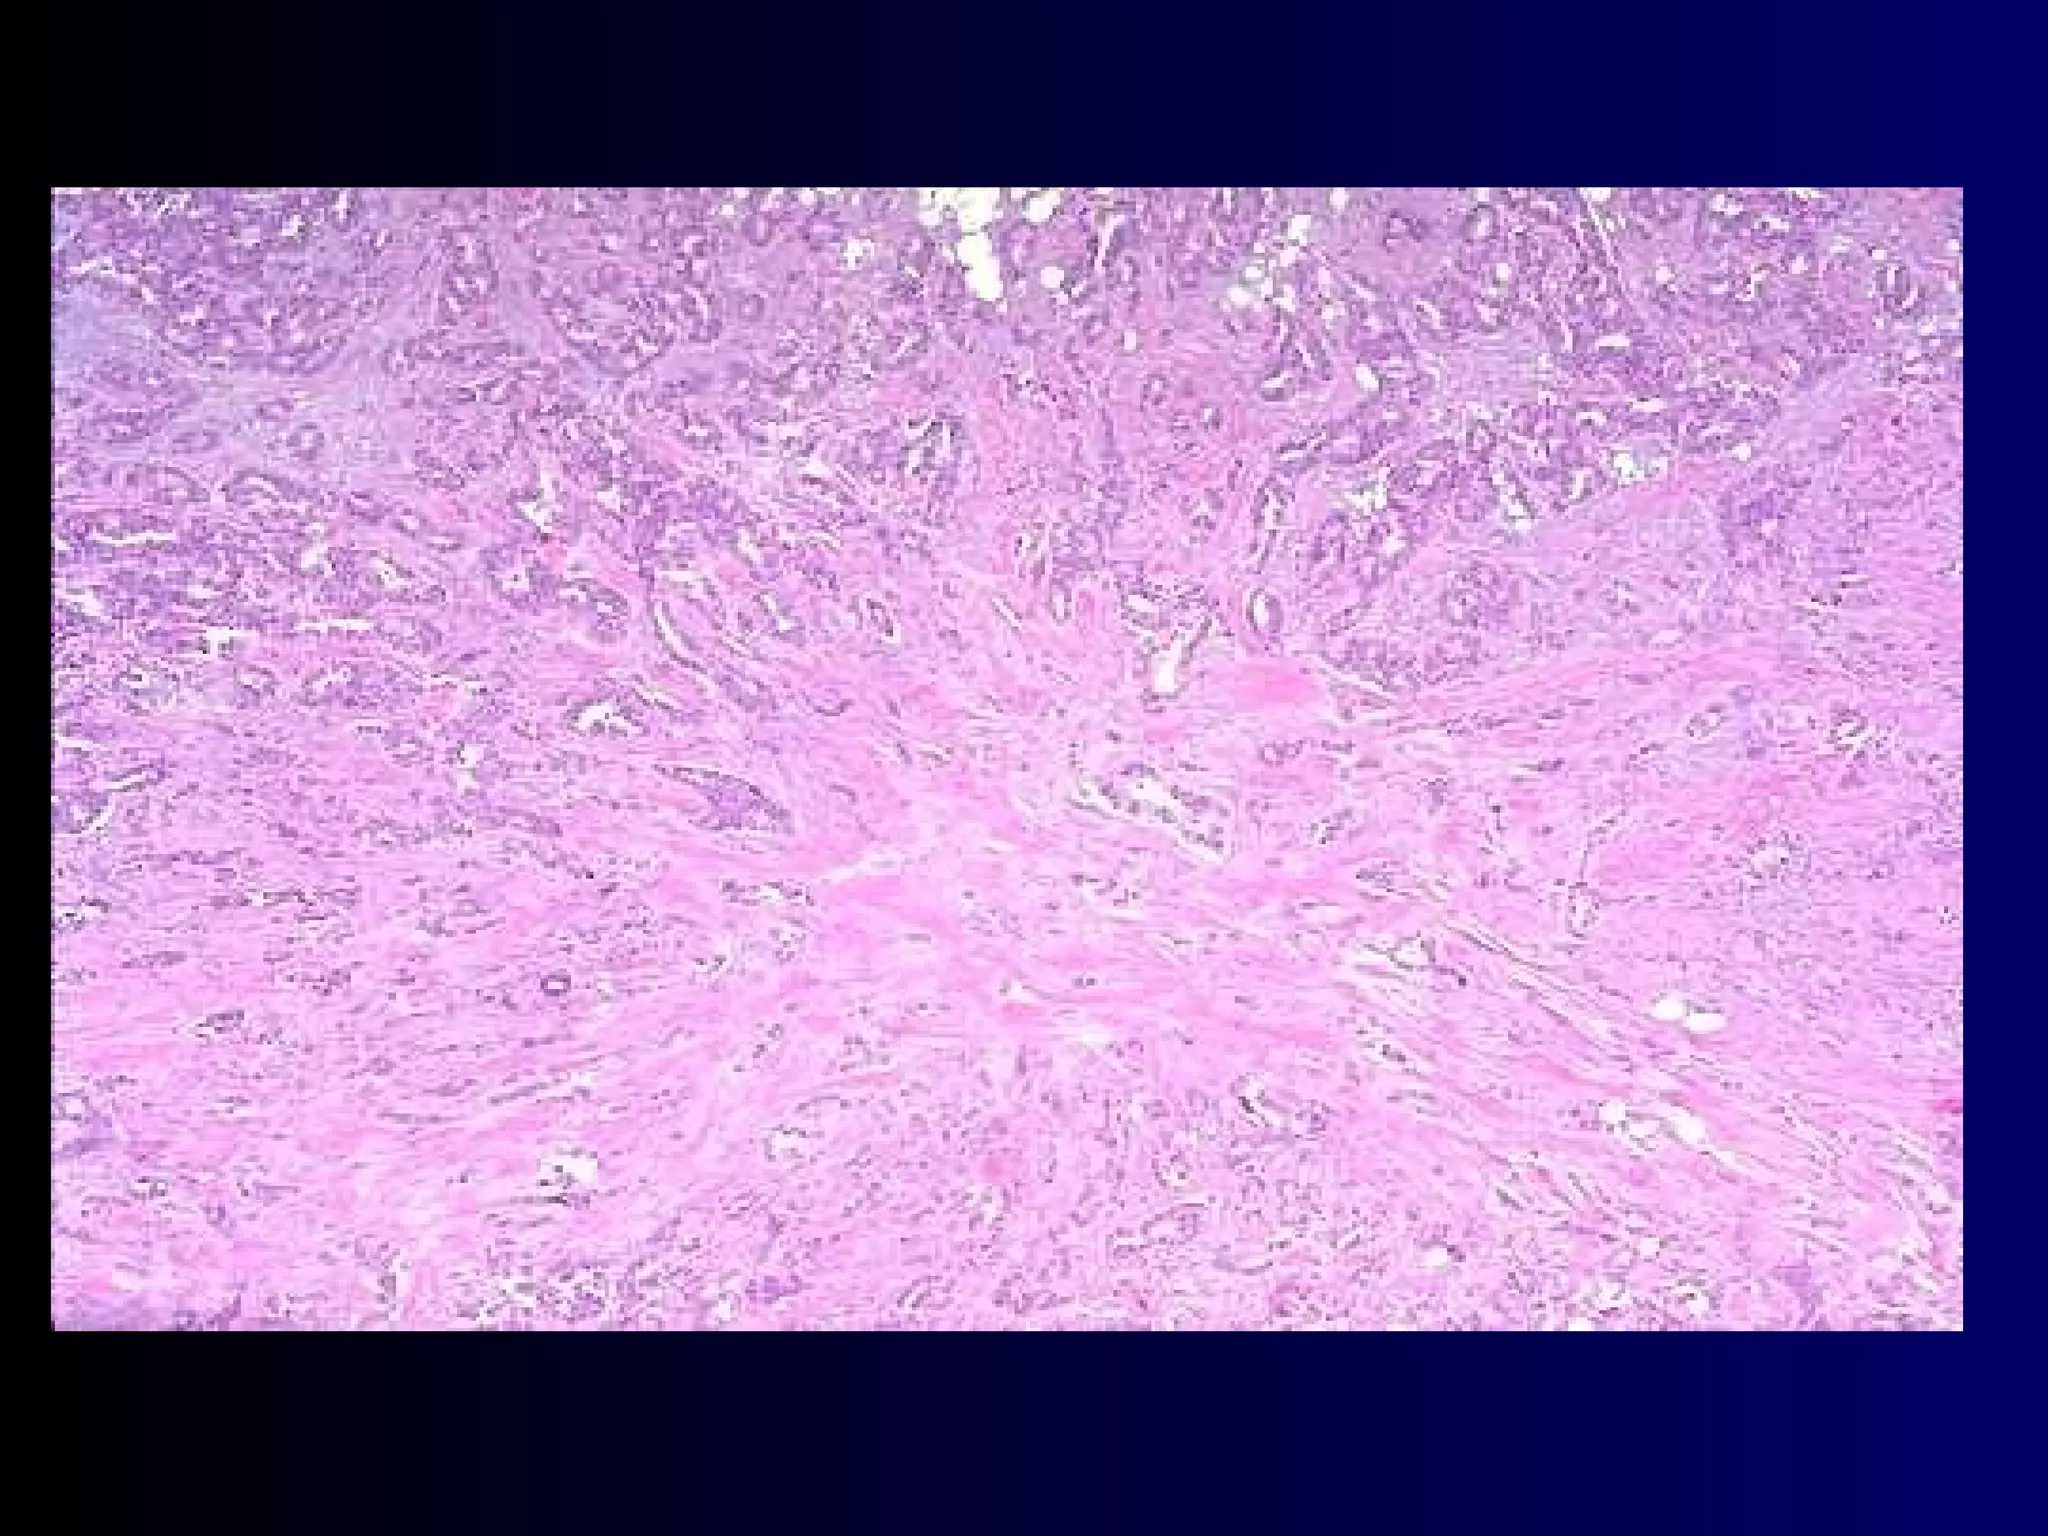

Diagnosis:  Carcinoma of the breast The invasive duct carcinoma usually has an abundant fibrous stroma, so it is also refered to as scirrhous carcinoma. Dense collagenous background

3 ) Cytology Single cells or clumps of cells exfoliated from their surrounding tissues.  Sputum, urine and abdominal fluid

Diagnosis: Carcinomaof the breast The invasive duct carcinoma usually has an abundant fibrous stroma, so it is also refered to as scirrhous carcinoma. Dense collagenous background